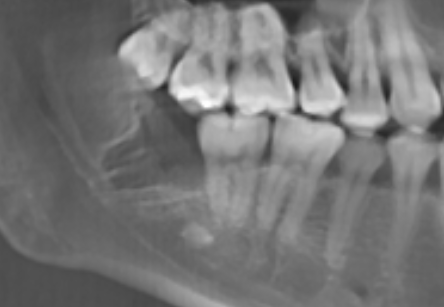

數位植牙的好處? 不管採取何種植牙治療方式,「4D微創導航系統」牙科技術能夠輔助醫師,在治療時,除了能透過醫師臨床的經驗與技術外,更能精準的控制與判斷病患的所有狀況,降低療程時可能發生的風險,以及減緩術後的不適感。 醫師會在病人的缺牙上,裝上一顆如同「監視器」的機器,搭配「4D動態導航系統」牙科技術,讓醫師在植牙的時候,能夠即時、精準的監測病人口腔骨頭內的狀況。 植牙有黃金治療時間嗎? 植牙的黃金治療期是「越來越快好!」為什麼是「越快越好呢?」最主要是因為牙齒與牙槽骨是相互依存的關係,當缺牙的第一年,骨頭會吸收得特別快,接下來每年以等比的速度吸收。 當口腔內的牙齒,有任何問題或是已經出現缺牙的情況,應該盡快尋求牙醫師的協助!進行治療與骨頭重建的需求評估,已避免增加重建的困難度,甚至無法治療。 到底適合「植牙」,還是要做利用兩邊牙齒做「牙橋」,最終還是需要經過醫師的專業判斷。 如何在茫茫醫海中,尋找適合的植牙醫師? 「一般牙科、贋復補綴科、口腔顎面外科、牙周專科」現代人很喜歡上網做功課,但想要找植牙醫師時,卻不知道從何尋找到適合的植牙醫師。 其實,能夠提供患者專業植牙技術的醫師,通常會受過「贋復補綴科、口腔顎面外科、牙周病科」這3大科的專業訓練。 擔心花錢後植牙出現問題又無法處理,如果長期看診的牙醫診所沒有相關的專業醫師,可以請醫師幫忙轉介。 另外,也可以挑選幾位自己喜歡的醫師,進行面診諮詢,找出最適合的醫師。最後,與醫師充分的溝通、配合也是植牙成功與否的重要關鍵。 植牙的步驟 植牙的流程大致可以分為幾個階段:資料蒐集、資料分析與重建理想牙位、植牙手術與植牙臨時假牙製作,以及最後最重要的植牙假牙製作。 植牙諮詢的第一步「資料蒐集」 資料蒐集、分析: 先利用口腔掃描機、臉部掃描儀、X光片、斷層掃描等,蒐集病患口腔整體環境、牙齦、骨頭的臨床資訊,以及紀錄顳顎關節與咬合的情況。 植牙手術 植牙手術:在經過專業的醫療團隊,進行術前評估後,以及擬定個人化的治療方針後,就會進入植牙手術的步驟,手術的步驟,會先進行牙齦翻瓣、鑽孔、植入人工牙根、縫合、拆線等。 不少人聽到上述步驟,或許已經頭皮發麻,專業的醫療團隊在治療的過程中,會搭配「舒眠麻醉」治療,能夠降低病患在過程中的不適感與恐聚感。 而通常人工牙根的癒合期大約需要6-12週的癒合,待癒合後才會進入「植牙臨時假牙製作」的製作。 植牙永久有效? 植牙有保固期 ? 「植牙成功後,就一勞永逸了嗎?就不用與醫師相見了嗎?」植牙它是鈦金屬釘子,植入骨頭癒合後,它不會蛀牙。但是,植牙周圍的牙肉跟骨頭,如果不妥善保養的話,還是會導致牙周病的發生,就是所謂的植體周圍炎。 植牙上方接出的牙冠,就好比買一台車,牙冠用久了,就如同車子用久了,零件、螺絲依舊會出現損毀的狀況,所以定期的回診保養追蹤是相當重要的。 通常植牙牙套完成後,至少半年回診一次,讓牙醫師檢查確認植牙附近牙齒沒有累積牙箘斑牙結石、植體周圍牙肉沒有發炎化膿,中間固定的螺絲沒有鬆動、牙套沒有破損、咬合狀況穩定等。 此外,患者必須維持良好的口腔清潔,可以參照之前我介紹的牙齒清潔方式,來保持好的口腔衛生、少抽菸等,如此搭配定期的回診檢查,可延長植體壽命。 植體的構造 植牙的治療過程很漫長,很多病患最常問的是「嘴巴內裝上的到底是什麼東西?」 今天的「植牙芯教室」就要帶你來認識「植牙整體的構造」(Dental implant) 口腔內的植牙由上→下依序是:牙冠、支台體、植體。 牙冠:又稱假牙冠、牙套,它是提供如同真牙的咀嚼功能,並且恢復美觀,永久性的牙冠最常見的材質為:全瓷、金屬合金、瓷熔合金屬。 支台齒:連接牙冠與植體的延伸部分,在中間點扮演重要角色,因為它必須要支撐牙冠的咬力,同時又要提供牙肉健康的生長環境,所以專科醫師在安裝時,必須依造病患口腔的狀況「客製化」的設計,ˊ尋找最適合的形狀、大小與角度。 植體:置入於缺牙的牙槽骨中,功能是取代原有的「牙根」,負責穩固牙齒的地基,目前最常見的植體材質為純鈦、鈦合金。 植牙x牙冠材質 對於越來越講求美觀的現代人來說,花錢植牙,當然希望它能美觀性與功能性兼具。 今天的「植牙芯教室」就要帶你來認識「牙冠材質」 目前,市面上永久性的牙冠最常見的材質為全瓷、金屬合金、瓷融合金屬 。 1.全瓷牙冠:材料有氧化鋯、強化玻璃瓷,不需要使用金屬,材質與人體的生物相容性高,同時具備高硬度的特性、高耐磨、耐高溫。在外觀上,呈色自然如同真牙,美觀性極佳。 2.瓷融合金屬牙冠:由於合金的成分複雜,若是高貴金屬的成分(黃金、白金)不夠高時,在口腔高溫潮溼的環境下,金屬容易腐蝕,導致表面粗糙,使牙菌斑難以徹底清潔,就容易造成牙齦發炎,並且染色,長期在美觀上、實用性都難以符合,對於外觀講求自然的病患。 3.金屬合金牙冠:由於整體採用金屬製作,所以不容易破裂、折斷,但是外觀呈現金屬色,所以當張開口時,便能夠一眼看出假牙的位置,如果使用金屬和金的牙冠,建議使用高貴金屬成分較高的材質。 植牙前的注意事項 想要提高植牙治療成功率,醫師與病患互相配合很重要,從術前的資料蒐集、評估與診斷,依據病人的情況,給予專屬的治療方針,從術中的治療過程,到術後的維護都非常重要,先來談談植牙前要注意那些事情。 1.保持口腔衛生:口腔清潔是植牙成功的最大關鍵 2.降低煙癮:抽菸會影響植牙的成功率,應該要盡量避免,如果能夠戒菸成功,更能提高植牙的成功率。 3.持續服用慢性病藥物:如果有在服用慢性病(高血壓、糖尿病等),在術前的諮詢,務必完整提供用藥歷史給醫師。 植牙後的潔牙步驟-工具篇 「植牙疏於潔牙與保健,百萬台幣立刻船過水無痕。」這是血淋淋的案例,真的不要以為,植牙完成後就一勞永逸。 術後的口腔清潔與維護非常重要!非常重要!非常重要!因為植牙的「使用壽命」,有非常大的關聯性。 植牙維護有三寶:牙刷、牙間刷、牙線 牙刷:可以選擇自己習慣的刷頭,或者選擇刷頭短小、刷毛軟硬適中的牙刷 牙間刷:當牙齦萎縮、牙縫變大時,應該選擇適合牙縫大小的牙間刷,用來清潔齒間的縫隙、牙套底層的牙菌斑與食物殘渣。 牙線:使用超級牙線,來清潔牙橋下的支柱牙部分。 漱口水、沖牙機等,這些只是輔助工具,千萬不能把它當作正規的潔牙器材。 植牙後的潔牙步驟-清潔篇 植牙的清潔方式。 首先:使用牙刷在假牙與牙肉的交界,採用刷牙法,來回輕刷至少10次。 接著:使用牙間刷,輕貼牙齒的表面,進行前後清洗,按照同一個方式,從舌側進入,輕貼牙齒表面,再做一次清潔,每次動作至少5次。 最後:使用大約45CM的牙線,可以使用穿引器的輔助,深入牙橋底下做清潔,每次動作至少5次。 植牙後的潔牙步驟-電動牙刷VS.一般牙刷 「做完牙套後可以用電動牙刷刷牙嗎?潔牙工具怎麼選?」上一篇,談了植牙的清潔方式,究竟植牙到底該不該用電動牙刷?答案是「可以」。 科學研究指出,使用電動牙刷,能更深入清潔到牙縫與牙齒倒凹處,尤其對於手部協調性沒那麼高的人,以及牙齒排列凌亂者,在清潔上能夠達到更好的效果。 刷頭的選擇:一樣要以刷頭小、刷毛軟硬度適中的刷頭,建議每1-3個月,或者外觀出現彎曲變形,刷頭就必須更換。千萬不要因為刷頭,比一般牙刷貴捨不得更換,反而會讓潔牙效果打折扣。 潔牙方式:電動牙刷與一般牙刷的潔牙方式的差異在於,電動牙刷只需要將刷頭輕放在單顆牙齒上,讓刷頭在牙齒與牙肉的交界處轉動,手不需要來回移動刷頭。但是千萬不要重壓,施壓過多的力道在牙齒上,反而對於牙齦是種傷害。 另外,不管使用電動牙刷或一般牙刷,都一定要使用牙線、牙間刷,來清潔牙齒與牙齒間的鄰接面,確保牙菌斑被清除。 潔牙時間:三餐飯後,30分鐘內如果能夠潔牙是最好的,如果無法達到,睡前徹底的潔牙是最重要!另外,潔牙時一定要有耐性,不要為了節省時間,隨便刷2.3下就結束。 如何選擇:預算、操作與攜帶方便度為首要考量,而且選擇具有「經濟部標準檢驗局」檢驗合格的產品,設計不良的電動牙刷,可能會造成口腔受傷。 植牙後的術後照護 植牙的最終成功與否,術後照顧真的非常重要!務必遵從醫囑,以下是照護的重點。 1.冰敷:術後1周,依舊會有些許的腫脹與輕微的瘀青,在48小時內,建議患者可以冰敷,在臉頰外側冰敷15-20分鐘,休息10分鐘,重覆動作到48小時。 2.不要泡溫泉、熱水澡,以及從事游泳與劇烈的運動。 3.飲食方面:初期還是會建議以流質、軟度高的食物為主,過燙、過冰的流質食物則不宜,應該避免食用過燙、辛辣、含有酒精成分刺激性的食物。 4.降低菸癮:為了讓植牙的傷口能順利恢復,醫學上皆有文獻記載,術後1周必須降低菸癮。 5.定期回診:植牙完成還是必須定期回診,讓醫師確認傷口、口腔健康的情形。 根據手術療程的不同,每一項術後的照護方式也有所差異,未來會跟大家分享與討論。 植牙後就能一勞永逸,不會有牙周病? 大多數的病患都知道,植牙前要先把牙周病及其他口內問題處理好,以降低口內細菌數量,才能夠進行植牙,但是很多病患以為,植牙成功,同時也能跟牙周病永久說再見,這觀念完全不正確。 簡單說「牙周病」是牙齒的周圍骨頭受到細菌的破壞,所造成的結果。因此,在植牙後,如果植體周遭的牙肉與骨頭,沒有得到妥善的清潔與照顧,還是會造成口腔內細菌的滋生,一樣會導致牙周病的發生。 植牙後,是不是也跟敏感性牙齒Say Bye Bye 一般所說的「敏感性牙齒」真正的學名是「牙本質知覺敏感症(Dentin Hypersensitivity)」會造成敏感性牙齒,主要原因是在於牙齒外層的琺瑯質被磨耗後,失去保護的功能; 或是牙齦萎縮牙根裸露時,都會造成牙本質內的神經小管暴露,當受到冷熱、吹氣、和壓力等刺激下,所產生的神經疼痛不適感。 植牙後,重建的人工牙冠內沒有神經,所以不會有敏感性牙齒的發生。然而,其他的自然牙齒,不會因為植牙而受到改變,當琺瑯質被破壞時,依舊會造成牙齒敏感性的問題。 骨質疏鬆的人適合植牙嗎? 「骨質疏鬆」有越來越年輕化的趨勢,除了因為年齡的增長之外,身體未獲得適當的保養也是元兇之一。如果是輕微的骨質疏鬆,只要適當的補充鈣質,想要植牙依舊沒有問題!整體還是必須交由專業醫師評估。 「骨鬆患者」,尤其是有在服用高劑量或施打抗蝕骨作用的藥物,是會影響植牙的成功率。原因在於,大多數的抗骨質疏鬆藥物,含有雙磷酸鹽,會影響骨骼細胞修補的功能,讓顎骨無法修復。所以如果有服用相關藥物,植牙前一定要告知醫師。 我是高血壓患者,能夠植牙嗎? 在高血壓控制好的前提下,是可以進行植牙手術的!正常的血壓是指收縮壓120/舒張壓80mmHg,當血壓偏高時,會增加手術中的出血狀況,提升手術的複雜度,甚至會提高手術後的感染率。 很多高血壓患者會服用「抗凝血藥物」。「抗凝血藥物」可能會在手術時,出現傷口流血不止的問題,所以醫師在進行植牙評估時,一定要讓醫師了解自身的慢性病史與用藥,並且盡可能尋找能提供詳細治療計畫,以及擅長微創植牙手術的醫師,降低植牙的風險。 我是糖尿病患者,能夠植牙嗎? 糖尿病患者與高血壓患者,都是在控制良好的前提下,能夠完成植牙手術。由於糖尿病控制不良的患者,細胞修復的能力與免疫系統,跟正常人比起來比較低,相對的牙周組織再生能力、傷口癒合情況也比較差。 所以想要植牙,必須同時與新陳代謝科醫師與植牙醫師相互合作,穩定血糖。除此之外,糖尿病患者也應該養成良好的口腔保健習慣,在經過醫師的專業評估,提供完善的治療計畫。 糖尿病與牙周病的關係? 「牙周病已經被列為糖尿病的併發症之一」前面談到「只要控制好血糖」依舊能夠植牙。我們也提到植牙前,一定要把牙周病控制住。今天我們就來談談「牙周病與糖尿病控制不良的關係」。 事實上,糖尿控制不良的病患發生牙周病的機率是正常人的3倍。最主要的原因,口腔細菌量會比正常人多,由於免疫系統比較差,更容易受到感染,所以傷口的復原能力也較低。 一旦糖尿病控制不良者得到牙周病時,病程也會跟著加速,骨頭被破壞與受損的速度也會加快。並且,因為身體長期發炎,將會導致血糖更不易控制。 癌症患者適合植牙嗎? 「癌症已經連續多年佔據國人10死因的首位」而癌症到底能不能進行植牙手術呢?首先,醫師會先了解病人的癌症種類與期數,以及過去的病史、治療史、用藥史,經由病人提供的資料,來做精準的判斷。 癌症的放射治療、免疫抑制等是會影響到傷口的癒合,治療上會使用到,抗骨吸收藥物 (antiresorptive agents)與抗血管生成藥物(antiangiogenic agent)等,都很有可能增加顎骨壞死的風險。另外,頭頸部經過放射線照射後,也會造成骨細胞的活性降低。 而且病人在接受化療、標靶藥物時,也會因為治療後,免疫力降低,細胞修復能力變弱,如果在治療期間,或是在治療後,想要做植牙,都應該先找醫師進行評估身體各項數值,以提高植牙成功率。 懷孕期間能夠植牙嗎? 雖然植牙是一個小手術,但是通常醫師都不會建議準媽咪們,在這時候進行植牙手術,首先,因為植牙是必須照X光檢查,在懷孕期間,應盡量避免暴露在輻射線下。 同時植牙必須經過麻醉的步驟,雖然麻藥會經由尿液排除體外,但大多數麻藥都含有「血管收縮劑」的成分,在治療過程中引發的加倍焦慮,可能會造成者子宮提前收縮的風險。所以會建議想植牙的準媽咪,產後再進行植牙手術。 產後、哺乳期植牙注意事項 「醫師,我正在哺乳期能植牙嗎?」在懷孕期間,就算已經完成第一階段的植牙手術,醫師為了保護母體與胎兒,會直接將療程暫停至產後,但是女性「產後要多久才能植牙?」、「哺乳期能植牙嗎?」成為許多媽媽最常問的問題。 事實上,女性產後的身體狀況恢復到一定的程度,就能夠進行植牙。而為了擔心麻醉藥或是抗生素、止痛藥分泌到母乳,加上每種藥物的半衰期不同,通常會建議,服用完最後一次藥物,在相隔24小時後,才進行哺乳。 服用健康食品是否會影響植牙 「維他命C、B群、魚油、銀杏、補鈣產品...」各式各樣的保健食品有吃有安心,很多病患到了診間,最常問我的問題之一「醫師,我有在服用各類的保健食品,會影響植牙嗎?」 事實上,需要看服用保健食品萃取的成分而定,不是所有的保養品食品,都會影響植牙的。如果營養品中含有「抗凝血作用」成分的保健食品,例如:銀杏、紅花。會建議在術前1周暫停服用。 雖然,適當的服用保健食品,確實有益於健康,但是在進行植牙評估時,還是務必告知,讓醫師做更正確的評估。 植牙要局部麻醉還是全身麻醉? 「植牙到底要全身麻醉,還是局部麻醉?麻醉的方式有哪些?差異性、有沒有後遺症?」許多病患都會有相同的疑問,從今天開始,一連串的文章來解惑。 其實,植牙手術跟一般口腔治療的方式一樣,能夠在病患清醒情況下進行治療,醫師通常會使用局部麻醉藥內含少比例血管收縮劑(Epinephrine),針對病人的手術內容,與治療所需的時間,給予準確的麻醉劑量。 由於大部分的局部麻醉藥,含有血管收縮劑,之前文章有提到高血壓的患者,必須在做治療諮詢時,提供用藥史與血壓控制情形,並且在手術當天,都應該接受血壓的測量,已確定用藥的安全性。 植牙的成功率?植牙失敗怎麼解?植牙的後遺症? 「植牙能100%成功嗎?植牙後是不是就再也不用回診?當植牙開始出現問題時,怎麼辦?植牙失敗後該如何治療?」這些問題是現在病患在選擇植牙時,很重要的考量。 「植牙成功率及植體壽命的長短」其實,最重要的是取決於醫師、病患有沒有合作無間,醫師與病患都應該在治療的過程中,扮演好彼此的角色,才能在植體成功骨整合後,延長使用的壽命。 病人,在諮詢時,要確實的將藥物史、病史提供給醫師。在治療期間,遵照醫囑、落實口腔衛生,並且在術後定期回診。此外,當植體出現任何情況時,必須立刻尋求醫師的協助「及早發現、及早治療」。 醫師,在技術、經驗上必須給予病患精準個人化的治療方針,並且選用大品牌的植體、生物醫材,提高治療成功率。同時,隨時吸收醫療新知,並將它運用,讓病患得到最好的治療。 上述都是植牙成功不可或缺的關鍵之一。 植牙後出狀況x牙冠瓷破裂 「植牙後出狀況怎麼辦?」 就如同之前所說,植牙就像是一部車子,用久了零件會出現受損的情況,要聊「出狀況怎麼辦?」就要回歸問題的根源來對症下藥,接下來,我將針對「植牙後常見的幾大狀況」來做詳細的說明: 牙冠瓷破裂:可將假牙取下,送修補瓷以回復美觀及咬合功能。因為牙科材料學的進步,新式二氧化鋯牙冠 (Zirconia),幾乎不會有破裂的狀況,這也是目前牙冠材質中,在品質與美觀上的表現,都擁有較高的穩定性。專業的贋復醫師在修復之前,會先把連接體跟牙冠中間的隙縫清潔乾淨,讓植體免於細菌感染的風險。 植牙後出狀況x植體配件的鬆脫、受損 「植體配件的鬆脫、受損」,之前的植牙芯教室,我們有介紹,牙冠與支台齒內含有各種不同的小零件,當植體用久了,零件開始出現狀況,該如何處理? 要談到該如何處置之前,要先了解,為什麼會發生「植體配件的鬆脫、受損」的狀況,大致可以把原因歸類為:零件壽命、植體長期咬合受力。 病患完成植牙後,在每半年的定期回診,牙醫師都會針對這些細部零件做確認,確定是否有鬆脫或晃動的情形出現。 一旦出現螺絲的鬆脫情況,沒有及時治療,螺絲就會斷裂在植體內,而要從植體內,將斷裂的螺絲取出,是件複雜又具高風險的療程,必須由經過專業訓練的植牙贋復科醫師來做處置,在往後的文章,將再做更詳細的說明。 植牙的麻醉方式有哪些? 「舒眠麻醉、全身麻醉、笑氣麻醉」這是目前大家在搜尋資料時,比較容尋找到的關鍵字,今天就來簡單介紹,這些麻醉的專有名詞。 舒眠麻醉:目前贋復科醫師最常使用的麻醉方式,屬於淺層麻醉,能夠讓病患在放鬆的情況下進行治療,也能夠降低局部麻醉的用藥量,關於「舒眠麻醉」接下來會一系列的介紹。 全身麻醉:屬於深度麻醉,麻醉藥的劑量會讓病患意識消失,而且無法自主呼吸,術後的恢復期較長,必須要在開刀房內進行。 笑氣麻醉:主要是用來鎮靜,而非麻醉,有些病患在做口內局部麻醉時,依舊會感受到看牙的緊張感,因此,有些醫院或診所,會備有笑氣設備,幫助病患在局部麻醉時,能夠鎮定。 植牙的評估要件懶人包 Q:缺牙會影響到那些層面? A:身體、心理都會受到影響,長期缺牙會讓導致「咬合障礙」 Q:到底要植牙,還是要做假牙? A:需要經過醫師的專業評估與判斷,「假牙」與「植牙」各有優、缺點。 Q:幾歲適合植牙? A:只要經過牙醫師臨床的評估,不管是25歲較年輕的缺牙病患,或者80歲的族群都能。 Q:如何在茫茫醫海中,尋找適合的植牙醫師? A:專業植牙技術的醫師通常會受過「贋復補綴科、口腔顎面外科、牙周病科」3大科的專業訓練。 Q:怕痛的人,如何進行植牙手術? A:現在也出現了「舒眠治療」,讓患者在治療上,大幅減低焦慮感。 Q:我是高血壓患者能植牙嗎? A:在高血壓控制好的前提下,是可以進行植牙手術的! Q:骨質疏鬆的人適合植牙嗎? A:如果是輕微的骨質疏鬆,只要適當的補充鈣質,想要植牙依舊沒有問題。 Q:癌症患者適合植牙嗎? A:在癌症治療期間或是在治療後,想要做植牙,都應該先找醫師進行評估身體各項數值,以提高植牙成功率。 Q:懷孕期間能夠植牙嗎? A:植牙必須經過麻醉的步驟,所以想植牙的準媽咪,產後再進行植牙手術。 Q:服用健康食品是否會影響植牙? A:需要看服用保健食品萃取的成分而定,不是所有的保養品食品,都會影響植牙的 舒眠治療懶人包 Q:舒眠治療有健保給付嗎? A:舒眠自療跟植牙如同屬於自費項目,並無健保給付。 Q:舒眠治療前需要做哪一些準備? A:由於治療藥物的濃度,與個人身體狀況與病史有關,所以患者必須確實告訴醫師用藥的習慣以及病史,必要時,在舒眠治療前,醫師會要求病患,先做身體健康檢查。 Q:平常有習慣吃保健食品需要暫停嗎? A:大部分的保健食品都不需要停藥。 Q:舒眠治療需要禁食嗎? A:需要的,必須至少禁食6-8小時,如果是在上午進行,前晚12時之後就不可飲食,如果是下午,則是早餐過後,就不能進食。 Q:舒眠治療前的禁食,若有需要服用藥物該怎麼辦? A:禁食期間,服用少量的水吃藥是被允許的。 Q:有服用抗凝血藥物怎麼辦? A:通常不需要停藥,除非是經過專業醫師指示,才需要停藥。 Q:舒眠治療當天可以駕駛嗎? A:舒眠完成後,可能會有頭暈的狀況出現,建議在親朋好友陪同下,搭乘交通工具前往診所。 Q:舒眠治療後的注意事項? A:在完成治療後,患者應休息20-30分鐘,確保沒有暈眩、嗜睡的情況發生,才能離開診所。 植體品牌 ║史得勞曼(Straumann)║ 瑞士的植牙品牌,經過許多臨床醫學研究證實,是植體品牌中邊緣骨流失最少的系統之一,其特殊植體連接體的設計,使牙冠與植體緊密結合,增加假牙的穩定度,降低鬆脫、晃動的機率。 →https://reurl.cc/8lDo1X ║諾保科(Nobel biocare)║ 瑞典的植牙品牌,在2008年推出的NobelActive系統,植體特殊的螺紋設計及表面處理,適用於骨質條件狀況比較複雜的患者。 →https://reurl.cc/xDN9zL ║亞仕特(Astra Tech Implant)║ 瑞典的植牙品牌,在植體與連結面的設計上,採用特殊的圓錐六角形內接式的設計,穩定的接口,能降低牙冠與支台齒,鬆脫的情形。 →https://reurl.cc/jd91bn ║百好(BIOHORIZONS)║ 來自美國的植體品牌,BioHorizons採用硬度、生物性較高的鈦合金材質,同時擁有特殊的Laser-lok專利技術,不僅能降低植體牙周病的發生機率,又達到兼顧美觀的功能。 →https://reurl.cc/YlYvZn ║貝格莎曼杜(BEGO Semados)║ 德國在地生根、製造生產超過125年的歷史悠久,植體表面特殊的TiPure技術,能夠幫助植體與齒槽骨結合,達到最大的整合功能,同時,也能幫助植體壽命的延長。 →https://reurl.cc/oD81ov” - 植牙後的保養 2026.01.19

X光檢查和電腦斷層掃描:

這些檢查可以幫助醫師更精確地了解患者的骨質密度和位置,以便進行更精確的手術規劃。